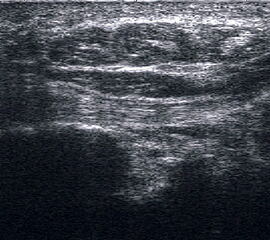

Ruptur Lig. fibulocalcaneare

Längsschnitt über dem Lig. fibulocalcaneare. Die Peronealsehnen erscheinen als echoreiche runde bis ovaläre Struktur.

Abbildung 19

Lagerung: Rückenlage, OSG in Neutralstellung.

Schnittebene: LS über Lig. fibulocalcaneare.

Referenzstrukturen: Fibulaspitze und Talus.

Befunde: Das Lig. fibulocalcaneare is nativ schlecht abgrenzbar, da es in die Tiefe und nicht parallel zum Schallkopf verläuft. Direkt über das Band ziehen quer getroffen die Peronäussehnen. Durch die Distorsion kann auch das Peritendineum peroneale einreißen. Die Peronealsehnen sind dann in ihrer Sehnenscheide von Blut umgeben, was sich als echoarmer Ring (Halo-Phänomen) darstellt und ein indirektes Zeichen für eine Verletzung des Lig. fibulocalcaneare ist.